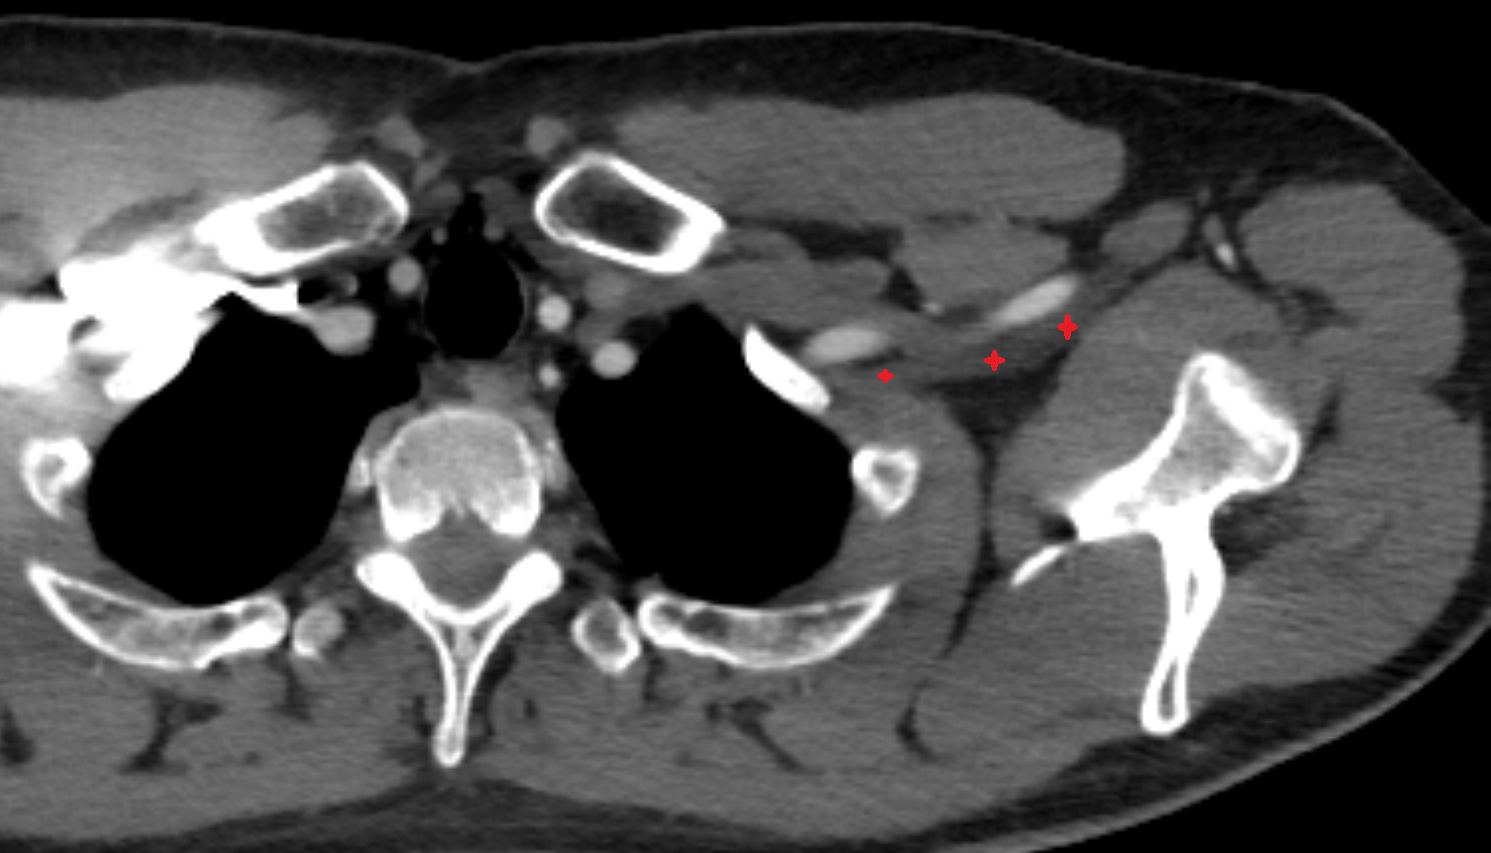

- Brachial plexus

- Cervical spinal nerve 5 (C5)

- Cervical spinal nerve 6 (C6)

- Scalenus anterior muscle (Anterior scalene muscle)

- Scalenus medius muscle (middle scalene muscle)